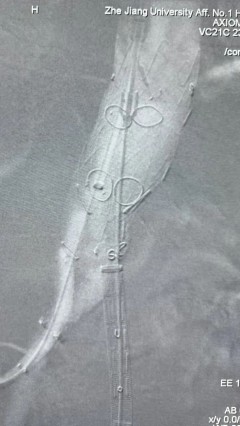

3. 经右股动脉导入超硬导丝,然后导入先健G-Branch 胸腹主动脉主体覆膜支架TAAA3418120e7i1010 一枚,释放主体支架至内分支打开,然后经左侧肱动脉入路,抓捕预置导丝成功后,将长鞘进入内分支出口处。

4. 经长鞘导入导管后,超选入腹腔干动脉,送入先健覆膜支架10*80mm一枚,近端重叠内分支,远端重叠腹腔干动脉,并予以10mm球囊后扩,手推造影显影良好。

5. 撤出腹腔干导丝导管,经左肱动脉长鞘继续抓捕预置导丝将长鞘超选至另一侧内分支,后超选进肠系膜上动脉,沿导丝送入先健覆膜支架10*100mm一枚,近端重叠内分支,远端重叠于肠系膜上动脉,并予以10mm球囊后扩,手推造影显影良好。

6. 解除束径,打开近端后释放,经肱动脉长鞘超选支架外分支,并进一步超选右侧肾动脉,交换加硬导丝,送入覆膜支架6*50mm和7*60mm各一枚,并予以球囊后扩张,手推造影显影良好。

7. 经长鞘重新选入左侧外分支,并超选进左肾动脉,沿导丝送入外周血管覆膜支架7*60mm一枚,并予以球囊后扩张,手推造影显影良好。

8. 从右侧股动脉入路送入腹主支架AB-24-12-110-S,近端重叠胸腹主动脉支架远端,调整好支架位置后释放。

9. 经左股动脉送入导丝导管,超选进腹主动脉支架短腿内,后沿导丝送入髂支,同理,右侧沿导丝送入髂支并释放,使用先健顺应性球囊后扩各支架连接处及支架近远端,最后通过预留导管向瘤腔注入人纤维蛋白粘合剂数支,造影显示分支通畅。